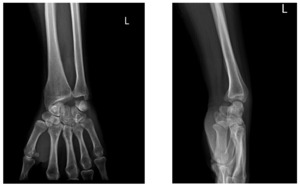

A 45-year-old woman sustained a left wrist injury in 2020 after a fall onto an outstretched hand. She was evaluated at a local facility, but a left lunate dislocation was missed. Two weeks prior to admission she developed atraumatic loss of active flexion of the left III and IV fingers. On examination, injury to the left flexor tendons of digits III and IV was suspected. Radiographs and CT scan demonstrated a volar dislocation of the lunate. The patient underwent surgery on October 1, 2024.

In our patient, the lunate dislocation had been neglected for 4 years. Preoperative radiographs and CT showed no radiocarpal degenerative changes. Intraoperatively, the FDS to digit IV had a short retraction with good tendon quality, allowing direct end-to-end repair; by contrast, the FDP to digits III and IV were retracted (~2 cm) with poor-quality ends. Accordingly, we performed lunate excision, direct repair of the FDS to digit IV, and reconstruction of the FDP to digits III and IV using an autologous palmaris longus tendon graft.